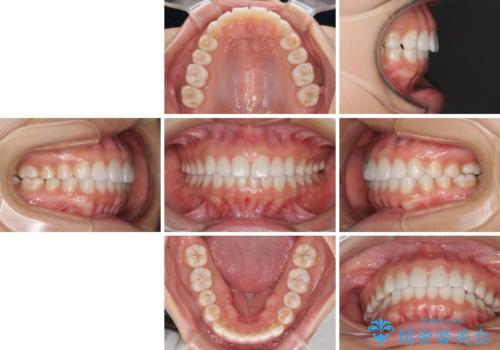

どこまで口元を引っ込めることができるのか、患者様自身も正直分からない部分があったため、少しずつ治療ゴールを変更しながら仕上げていきました。

気になっていた前歯の飛び出した印象は、最終的にはスッキリと引っ込み、大変満足していただきました。